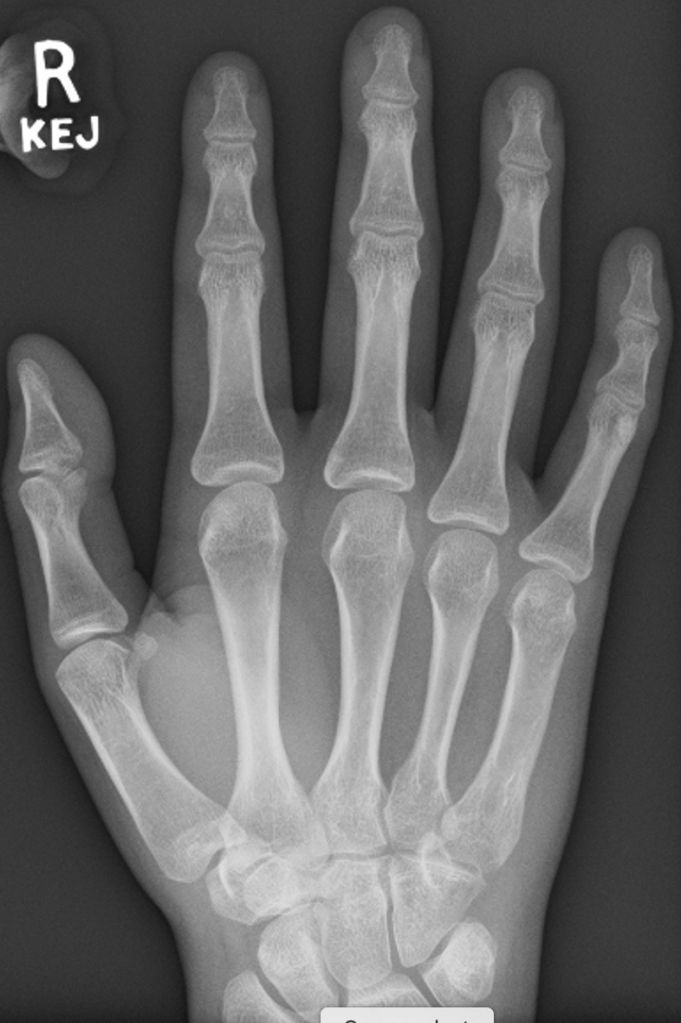

Loss of joint Space

In young patients, there are thick cartilage caps on the ends of the bones within the small joints of the hand. With age, these cartilage caps slowly wear from constant use, despite the body’s regenerative processes. A normal joint, therefore, has much less cartilage at 50 than at 20, and by the time people reach 80+ years, there is often very little cartilage left.

The GAP between the bones on an xray represents the space occupied by the cartilage, and it is very easy to predict how much cartilage is left in a joint simply by looking at the amount of space between the bones – the more space the more cartilage, and generally speaking the more healthy the joint.